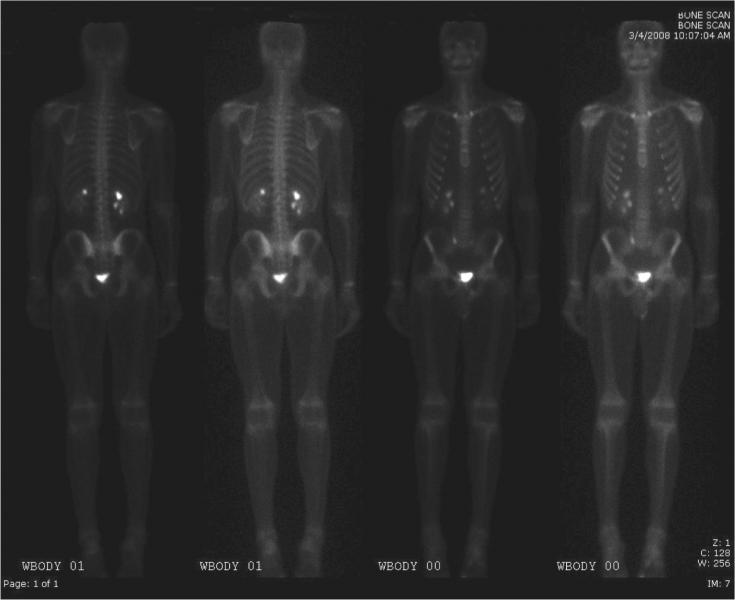

A new study finds men with prostate cancer that has spread to nearby lymph nodes can benefit from the addition of radiation therapy to treatments that block the effects of testosterone. This combination therapy would be most effective in patients at significant risk of dying from node-positive prostate cancer. The report from investigators at the Massachusetts General Hospital (MGH) Cancer Center and the American Cancer Society has been published online in the Journal of the National Cancer Institute.